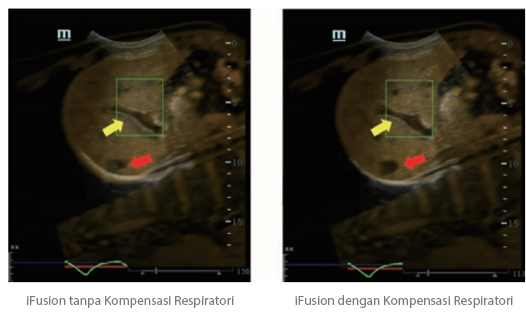

Sejak didirikan, Mindray terus mencari cara baru untuk meningkatkan keandalan diagnostik. Didukung Teknologi ZONE Sonography? terkini, platform ZST+ baru Resona 7 meningkatkan kualitas gambar ultrasound melalui pengambilan zona dan pemrosesan data saluran.

Selain kualitas gambar premium, Resona 7 juga meningkatkan kemampuan penelitian klinis dengan V Flow revolusioner untuk evaluasi hemodinamika vaskular, serta pengambilan penampang tercanggih dari rangkaian data 3D untuk diagnosis CNS pada janin. Kombinasi pengoperasian multisentuh berbasis gerakan yang paling intuitif dengan semua fitur klinis penting membuat Resona 7 menjadi gebrakan baru dalam inovasi ultrasound.